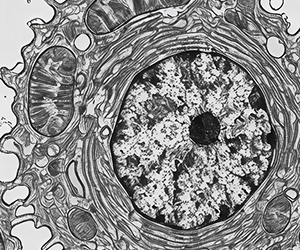

인체는 매일 100억 개의 세포가 만들어지고 사멸하며 균형을 유지합니다.

하지만 노화, 스트레스, 발암물질, 염증, 독소 등으로 손상 속도가 빨리지면

자연 재생시스템만으로는 회복이 어려워지며 노화(Aging)가 진행됩니다.

줄기세포 기반 재생치료를 통해 자가 재생 능력을 가진 줄기세포와

고농축, 고효율 재생 인자가 더해져 재생 환경(Niche)을 만들어

신체 노화를 돌리고 기능을 정상화 합니다.

성체 줄기세포

노화 세포 대체 및

손상 조직 스스로 찾아가

재생 주도

성분 : 자가 성체 줄기세포

(Autologus Adult Stem Cell)